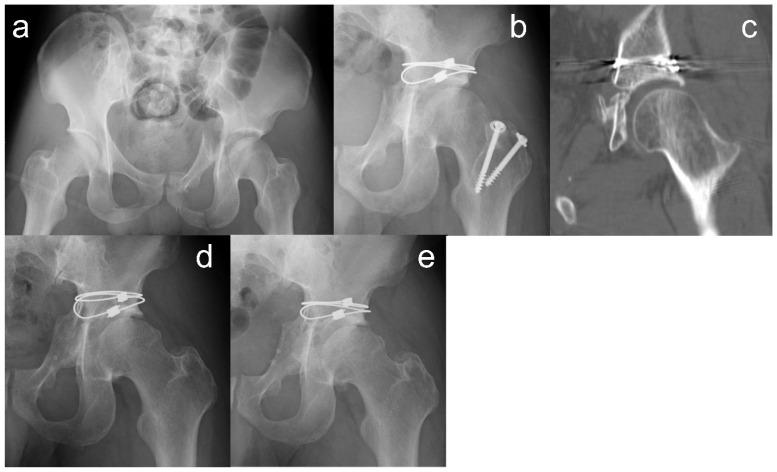

: Cerclage cable fixation with 2 mm multiple-braided cables for displaced acetabular fractures has shown good midterm functional and radiographic outcomes. We retrospectively evaluated the clinical and radiographic outcomes of cerclage cable fixations over ten years. : We extracted data for patients who underwent cerclage cable fixation for acetabular fractures at a single institution from 2007 to 2012. We adopted this procedure for acetabulum fractures with posterior column fractures. Postoperative reduction quality, complications, reoperations, and Japanese Orthopedic Association (JOA) hip objective functional scores were analyzed. Postoperative reduction quality was classified using plain radiography and computed tomography. : We evaluated nine patients with a mean follow-up period of 14.1 ± 2.6 years (range: 10.8-18.1 years). The mean age was 47.1 ± 15.5 years old (range: 28-74 years); the mean injury severity score was 13.6 ± 4.7 (range: 9-22). The most frequent type of fracture was a both-column fracture. Anatomical reduction quality was achieved in five cases. Four patients had hip osteoarthritis at the last follow-up; among them, one patient had worsening hip arthritis > 5 years after surgery, and one patient developed osteoarthritis > 10 years after surgery. Their postoperative reduction quality was worse than their anatomical reduction quality, and both engaged in physical labor. None of the patients underwent revision total hip arthroplasty. The mean JOA hip score was 90.9 ± 7.9 (range: 74-100); seven patients scored >90 at the last follow-up. : Cerclage cable fixation showed satisfactory postoperative reductions and favorable long-term clinical outcomes. Long-term follow-up might be necessary for patients whose postoperative reduction is not anatomical to detect late occurrence of hip osteoarthritis, even if osteoarthritis is not evident during short-term follow-up periods.

: 对于髋臼骨折,采用 2mm 多股编织线进行环扎电缆固定,中期功能和影像学结果良好。我们回顾性评估了单一机构在十年间采用环扎电缆固定治疗髋臼骨折的临床和影像学结果。: 我们提取了 2007 年至 2012 年期间在一家机构接受环扎电缆固定治疗髋臼骨折的患者数据。我们采用这种方法治疗后柱骨折的髋臼骨折。分析了术后复位质量、并发症、再次手术和日本骨科协会(JOA)髋关节客观功能评分。术后复位质量采用 X 线和平扫 CT 进行分类。: 我们评估了 9 例患者,平均随访时间为 14.1 ± 2.6 年(范围:10.8-18.1 年)。平均年龄为 47.1 ± 15.5 岁(范围:28-74 岁);平均损伤严重程度评分为 13.6 ± 4.7(范围:9-22)。最常见的骨折类型为双柱骨折。5 例达到解剖复位质量。4 例患者在末次随访时患有髋关节骨关节炎;其中 1 例患者术后 5 年以上髋关节关节炎加重,1 例患者术后 10 年以上出现骨关节炎。他们的术后复位质量比解剖复位质量差,且均从事体力劳动。所有患者均未接受翻修全髋关节置换术。JOA 髋关节评分为 90.9 ± 7.9(范围:74-100);7 例患者在末次随访时评分 >90。: 环扎电缆固定术后复位满意,长期临床效果良好。对于术后复位不是解剖复位的患者,需要长期随访,以发现晚期髋关节骨关节炎的发生,即使在短期随访期间没有明显的骨关节炎。